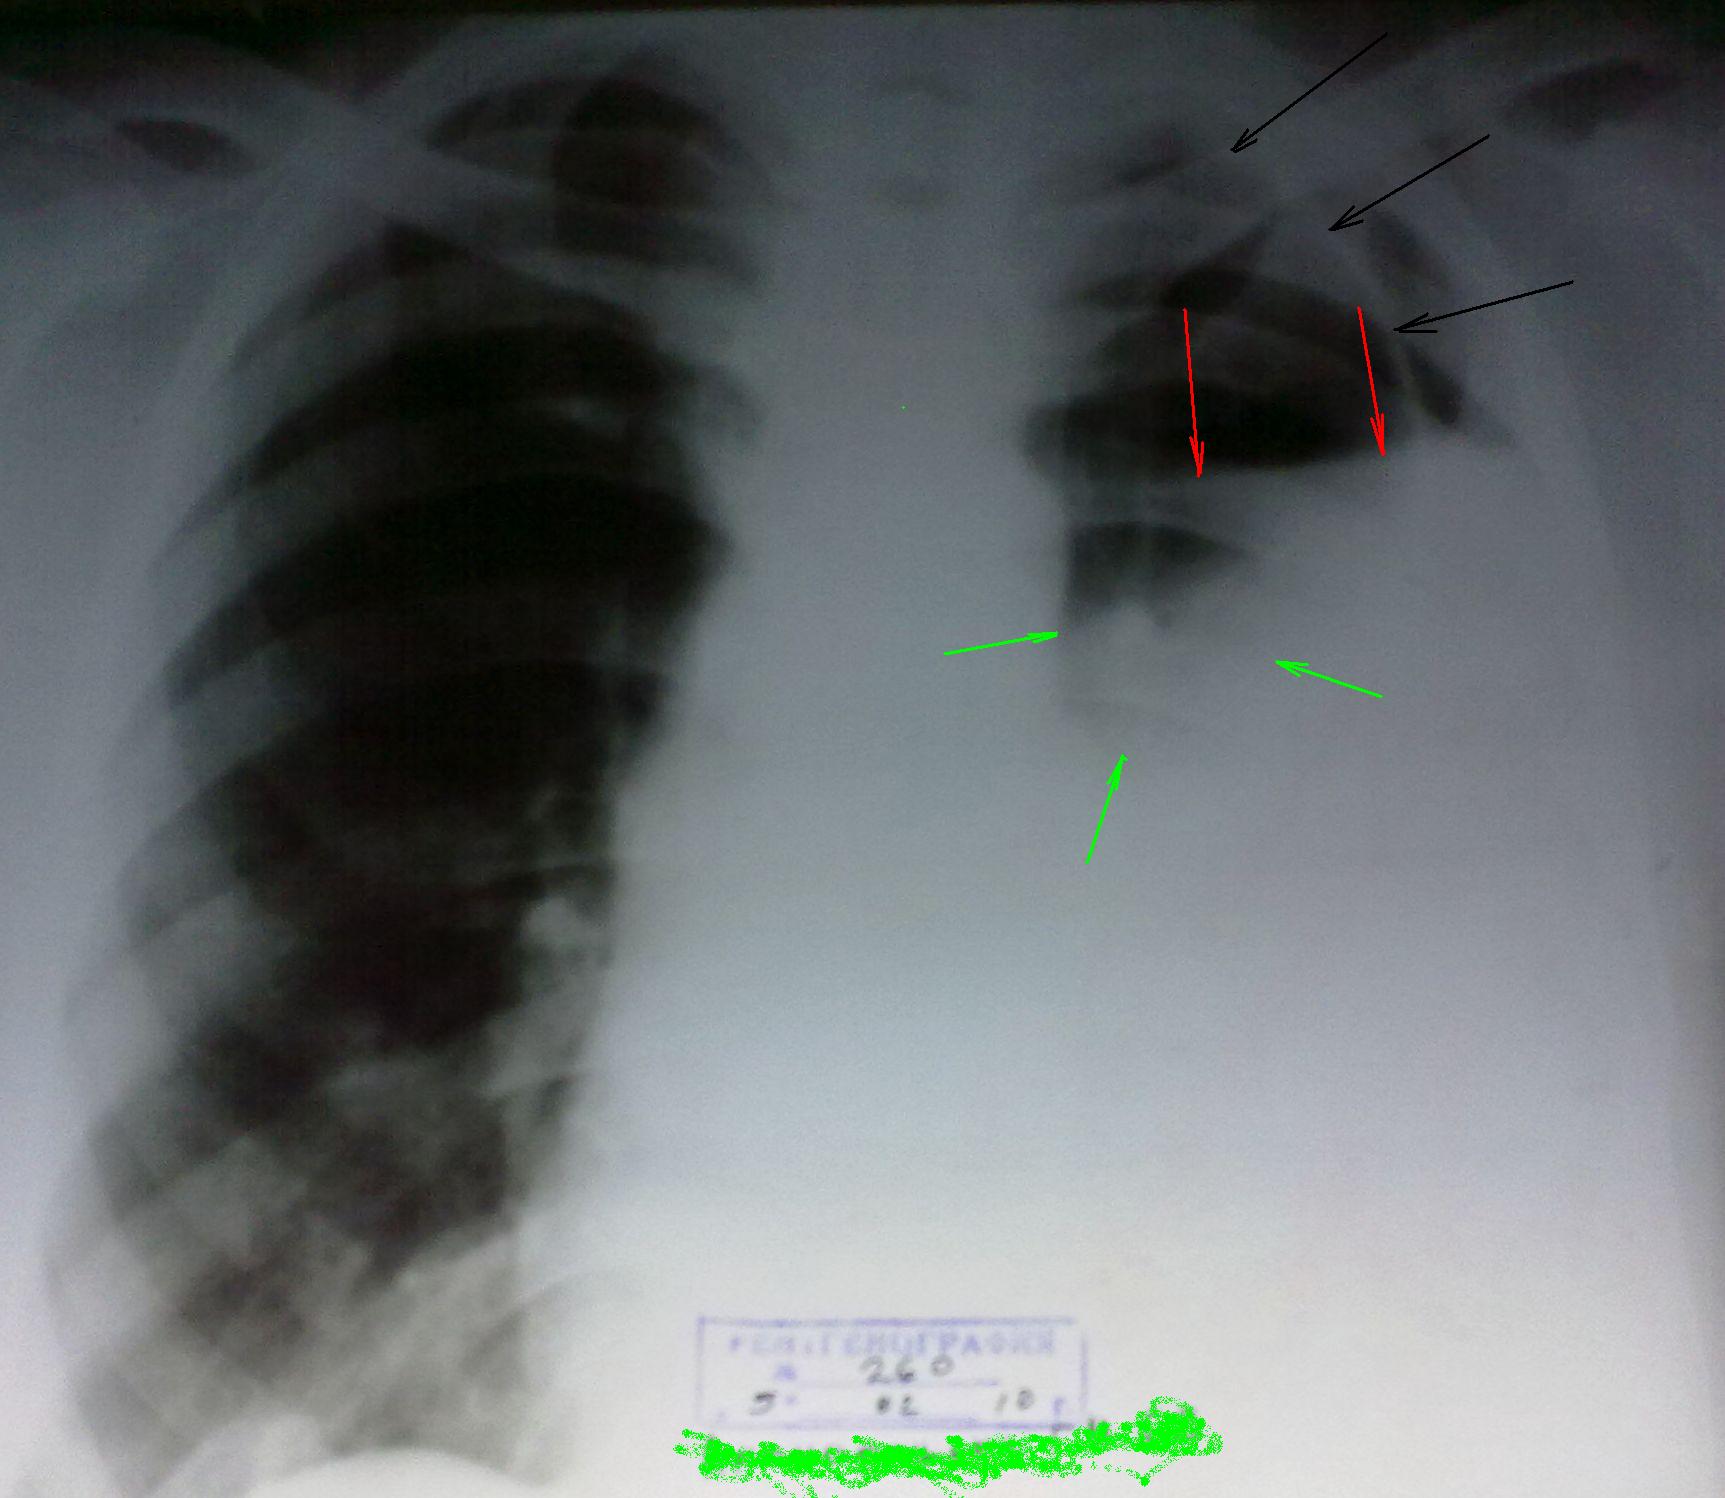

Эмпиема плевры.

Буквально пятничный случай. Хотел закрутить небольшую интригу, но потеряна вся информативность снимка при фотографировании, хотя рентгенограммы довольно качественные. Больная, любительница бахуса, поступила в тяжелом состоянии. В прошлом заболевания легких отрицает. Не мог решить, как могла скиалогически образоваться такая картина. Что это за линейная тень, отмеченная черными стрелками (если это край легкого - пневмоторакс, то против этого недостаточная чернота зоны, латеральнее нее). Горизонтальная линия, отмеченная красными стрелками вроде говорит за гидропневмоторакс, но как объяснить просветление, отмеченное зелеными стрелками. Все таки написал плеврит. Пневмоторакс? При плевральной пункции получили 2,5 литра вязкой гноеподобной жидкости. Настораживает резкое обеднение легочного рисунка на больной стороне, хотя справа на рентгенограмме он хорошо прослеживается, с легким склерозом.

Дама, по всей видимости травмировалась, к примеру - перелом ребер, но боли, возможно, достаточно не ощутила, ну, если всегда под анальгетиком, вполне понятно. За переломом ребра (ребер) возник посттравматический пневмоторакс, присоединилась инфекция, а возможно и кровушка, возникла картина "хронического пнемоторакса", присоединилась эмпиема плевры, возможно по типу ступенчатого пневмоплеврита. Затем, запустился процесс швартообразования.

В дальнейшем, после пункции, оказалось, что "поезд - ушел". Адгезивный процесс, швартообразование, настолько хорошо фиксировали частично коллабированное левое легкое, что оно просто физически из-за сращений расправиться не может. Костальная плевра также утолщена с наложениями, что и создает впечатление "обедненного легочного" рисунка, на фоне участка пневмоторакса, т.е. там, где легкого фактически нет. Запаяны и синусы плевры, по всей видимости фиксирована, и диафрагма.